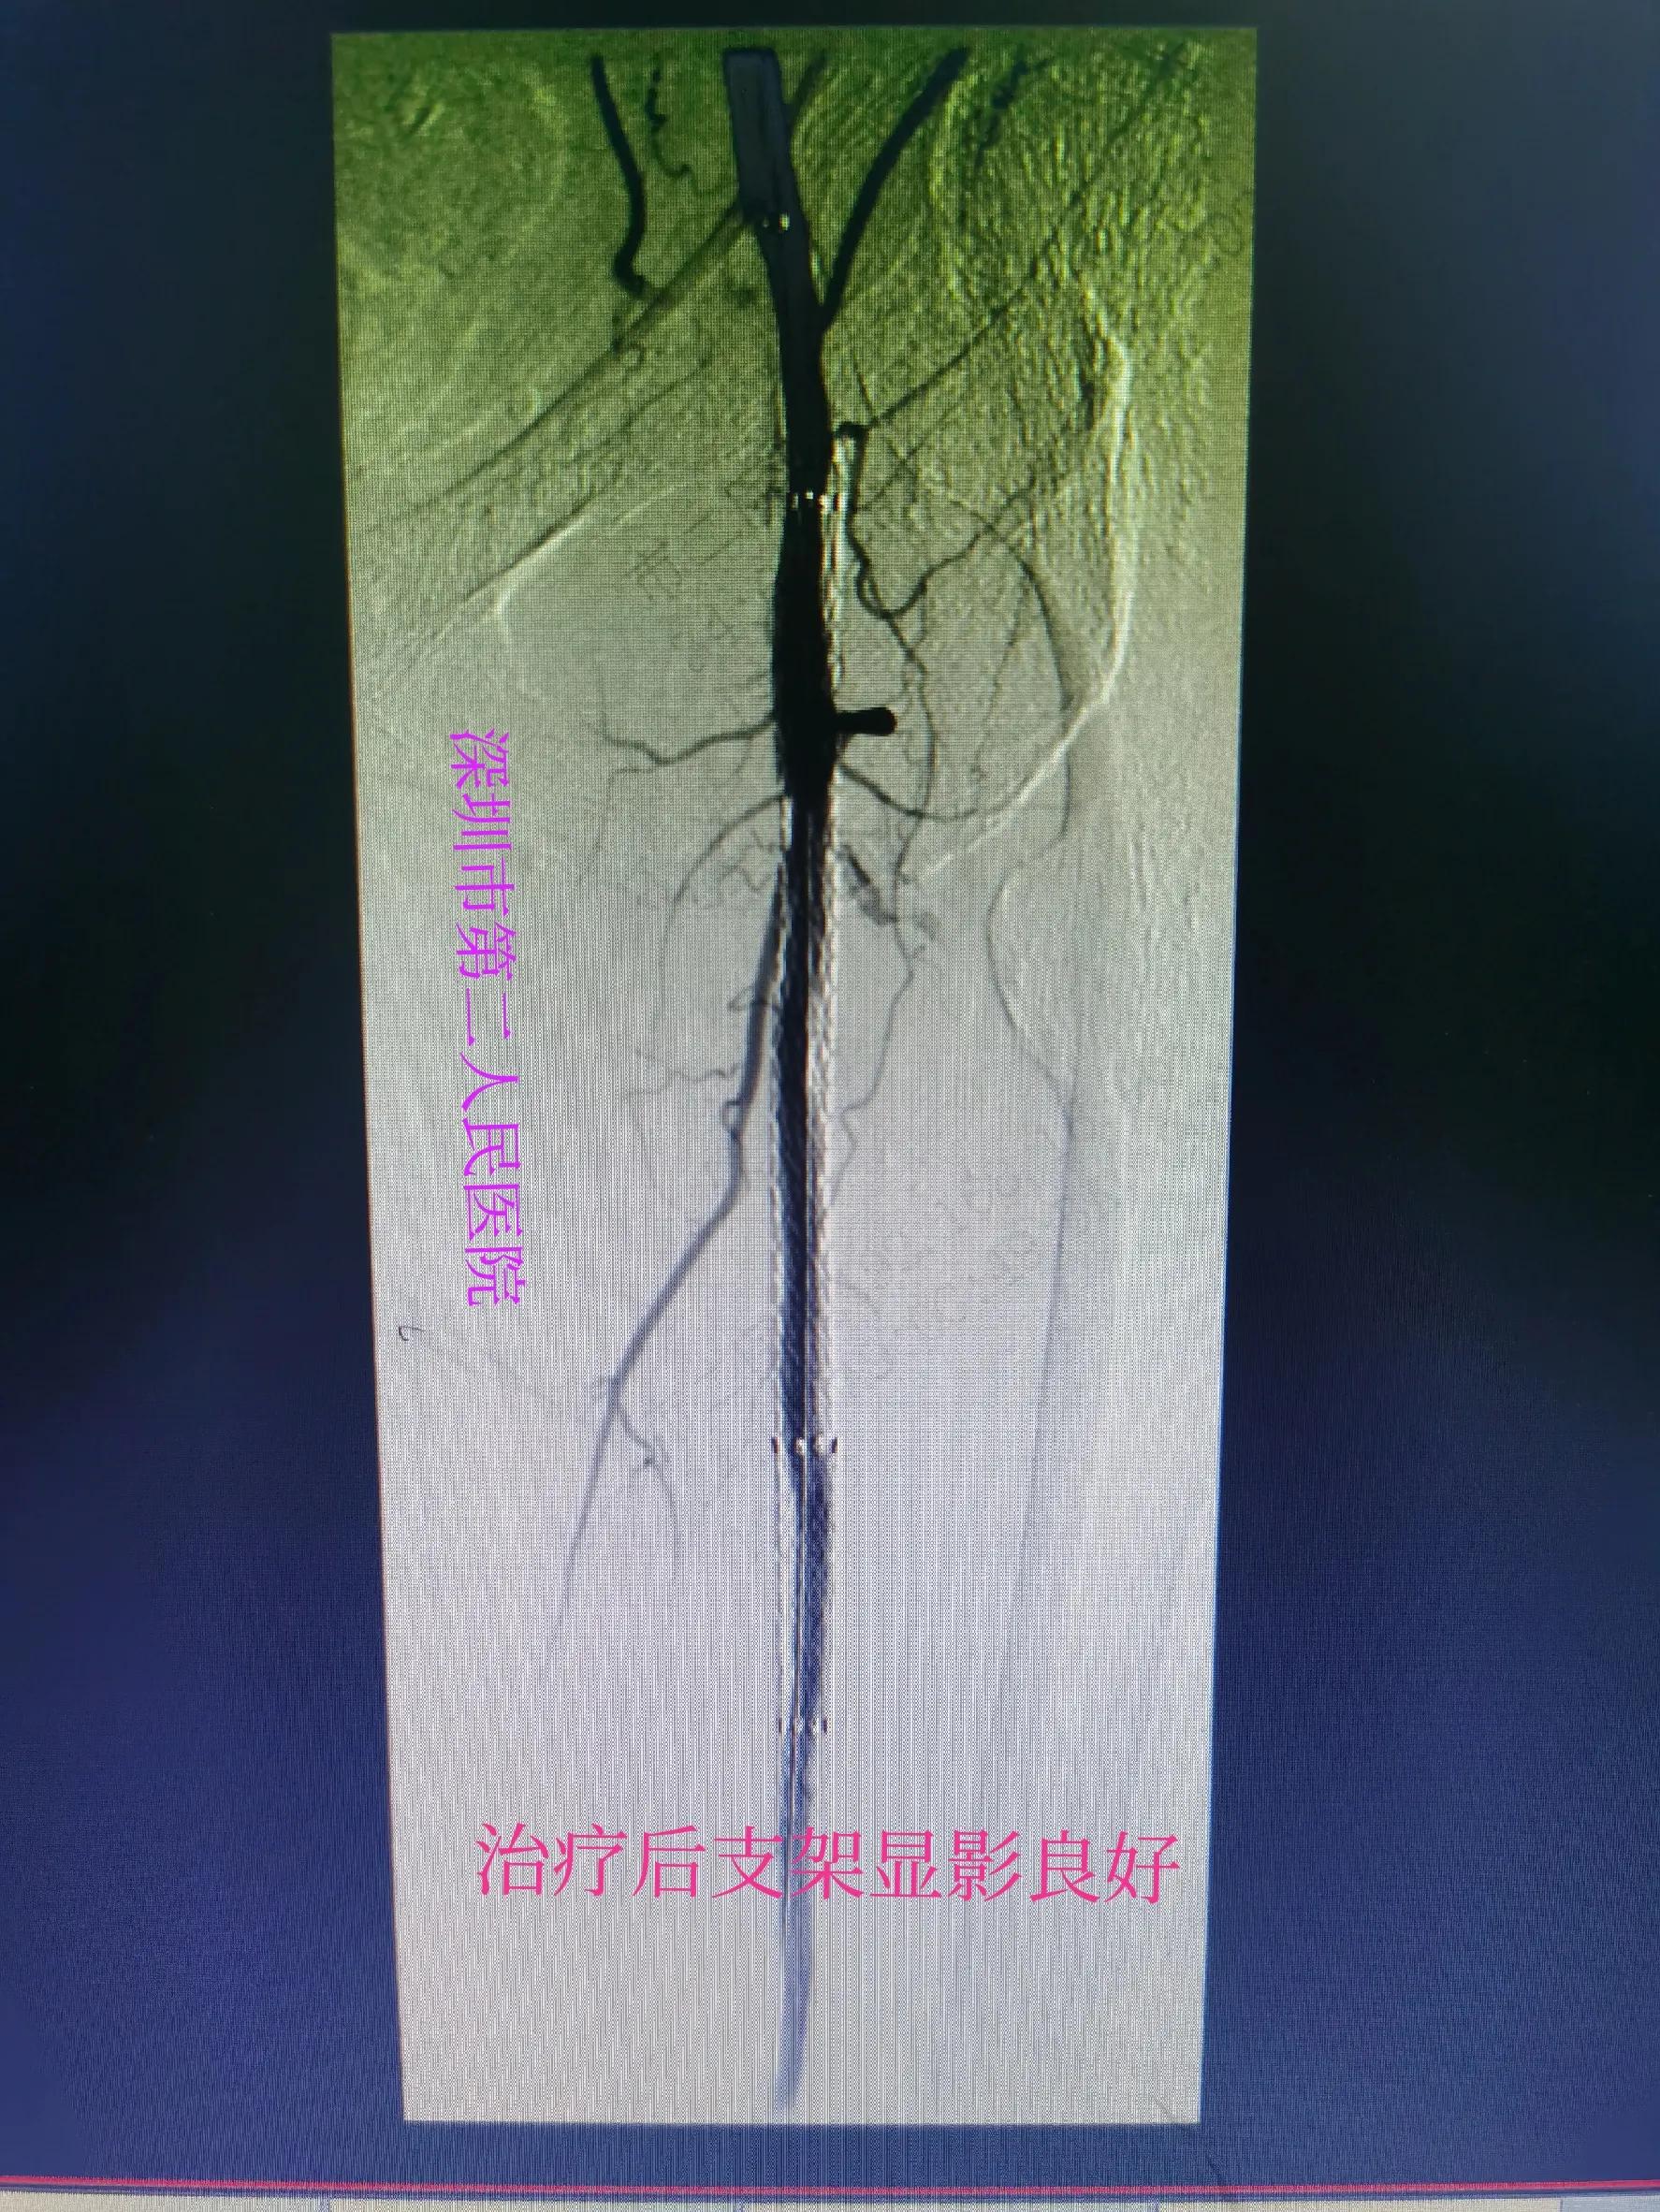

经过三个多小时的积极药物溶血栓、球囊扩张等治疗后,病人左小腿血流恢复,左足背动脉搏动良好。病人疼痛缓解,足部皮温恢复正常,比右腿还好。以下附上术前术后检查对比图。

支架内通畅